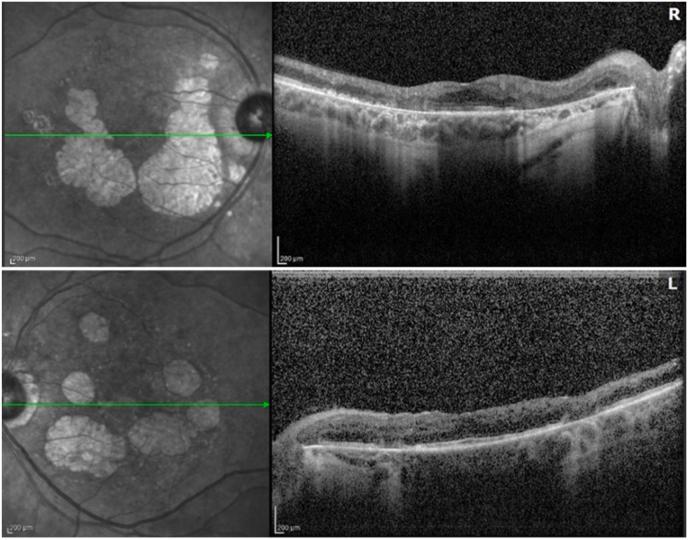

Neovascular Glaucoma in MELAS syndrome.

We present a rare case of neovascular glaucoma in a patient with MELAS with a history of diabetes, hearing loss, and macular dystrophy. MELAS should be suspected in patients with this constellation of symptoms.

我们报告了一例患有MELAS且有糖尿病、听力丧失和黄斑营养不良病史的患者发生新生血管性青光眼的罕见病例。出现这一系列症状的患者应怀疑患有MELAS。